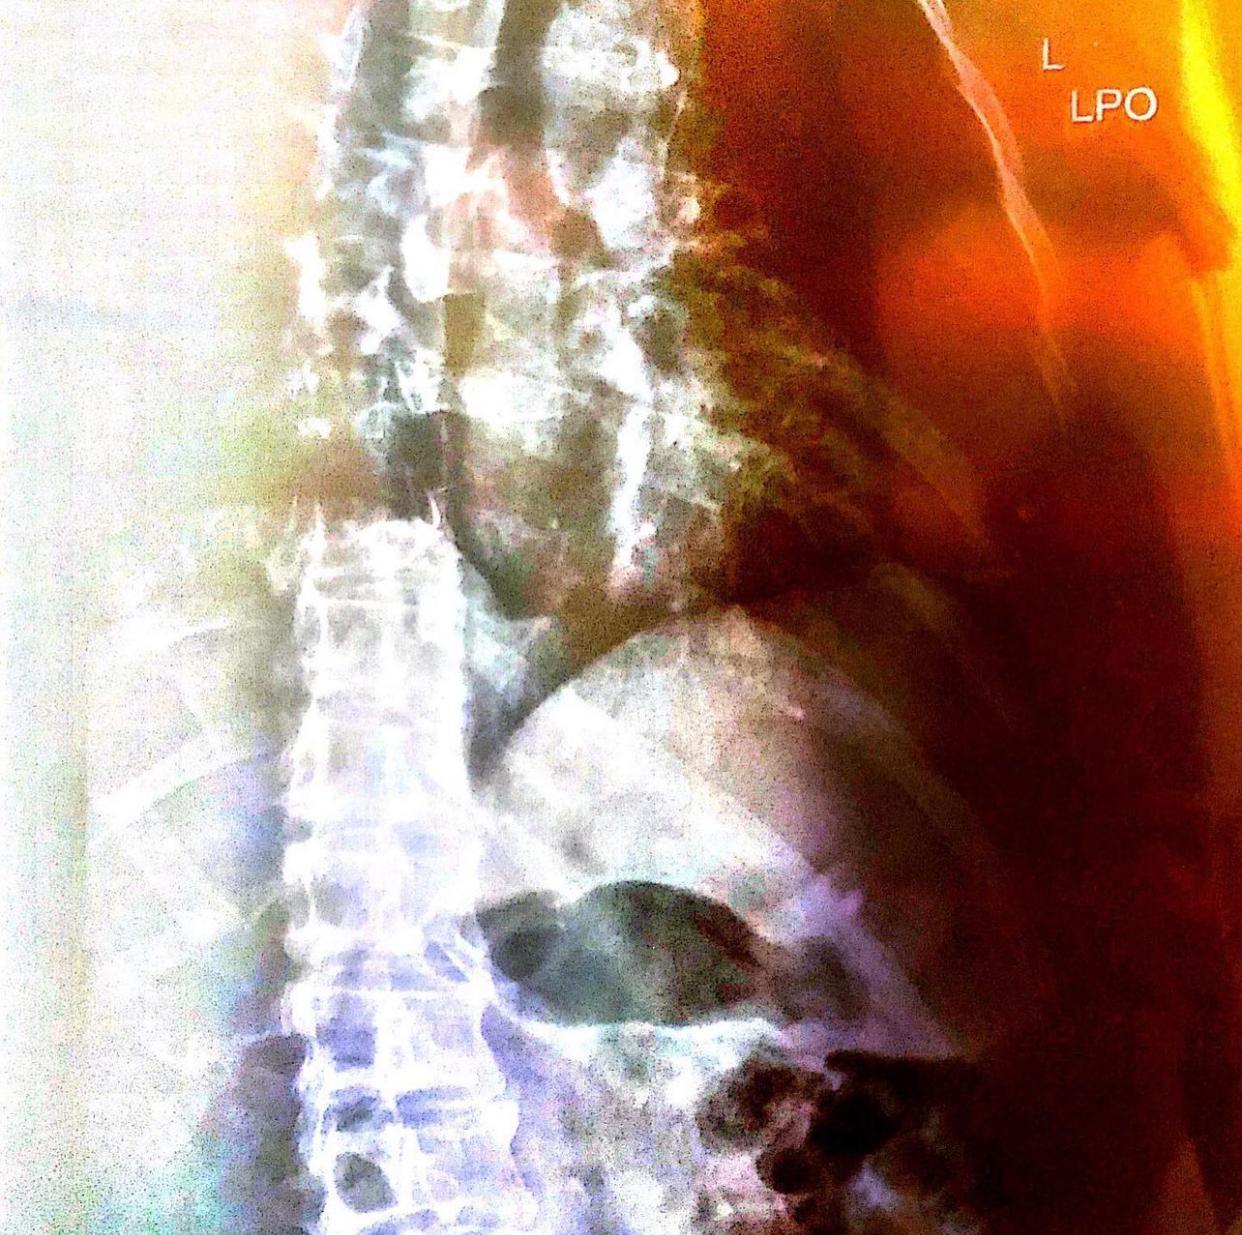

一連三天的《Clockenflap音樂節》假中環海濱舉行,昨晚由英國勁旅Pulp擔任壓軸嘉賓,登場時以《I Spy》一曲打頭陣,主音Jarvis Cocker用廣東話打招呼:「我哋係Pulp,你哋係Hong Kong!」Jarvis透露自己今次行程不慎跌落樓梯導致斷骨,更把X光片展示台上的大螢幕上,並提到低音結他手Steve Mackey今年3月不幸離世,令巡迴一度受挫。及後即唱出《Disco 2000》,全晚一小時還演繹《Something Changed》、《Joyriders》、《Common People》等名曲,在臨散場前,Jarvis以廣東話講:「多謝晒」,獲觀眾報以熱烈歡呼聲及掌聲。完騷後,Jarvis Cocker在社交平台公開X光片,表示在港碌落樓梯下弄斷兩條肋骨,幸得醫護人員悉心護理,令他可以如期演出,不忘大讚香港是個奇蹟。